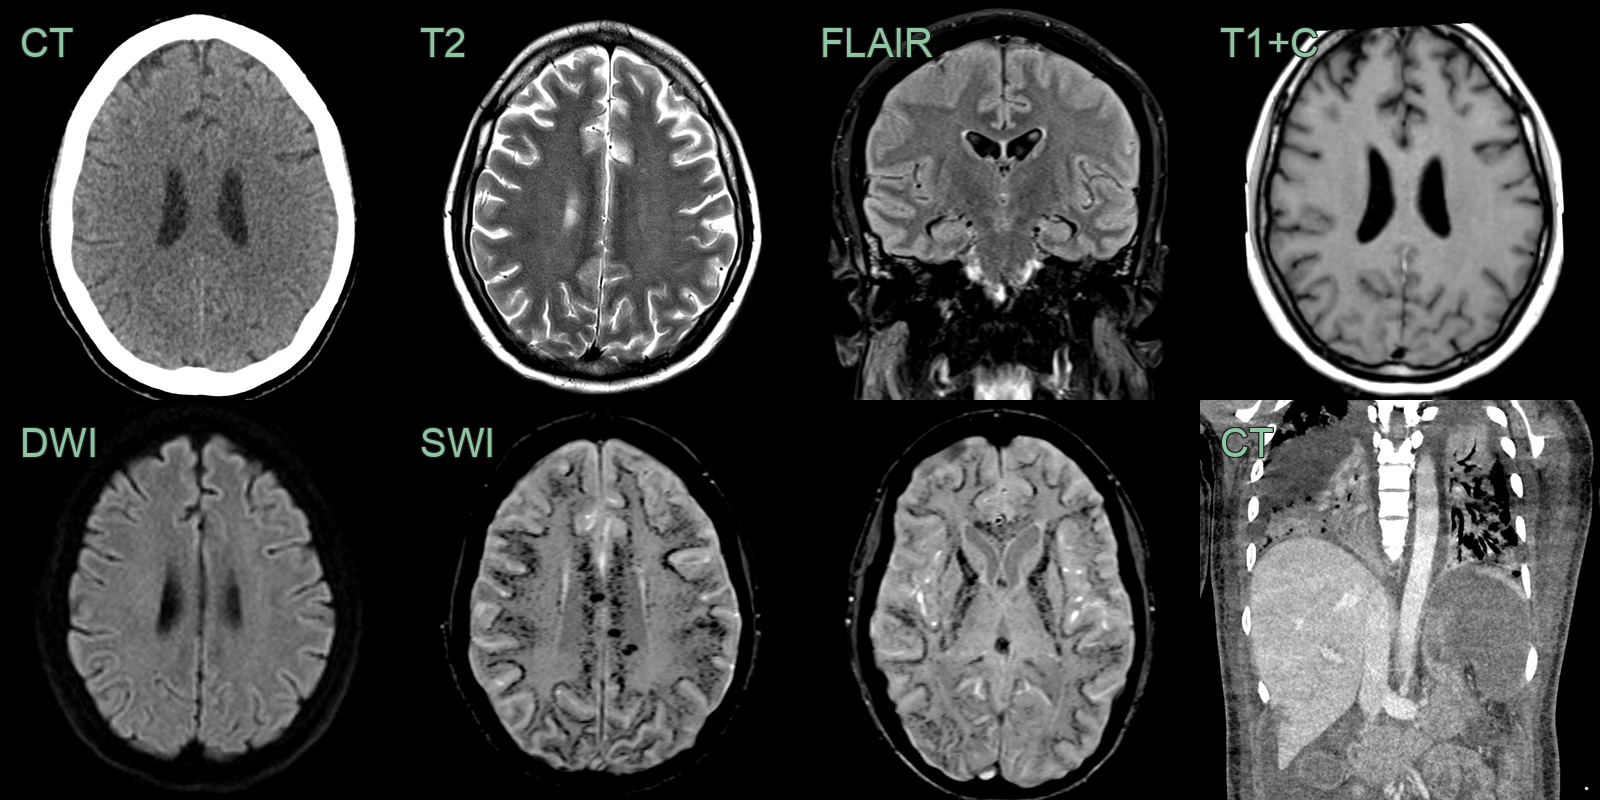

- A 40-year-old patient became obtunded 1 month after return from a region endemic for malaria.

- MRI showed the brain parenchyma appearing normal on T2 and FLAIR and DWI - there was no edema or ischemic changes.

- However, SWI showed extensive juxtacortical and deep white matter foci of susceptibility artefact (representing microhemorrhages and/or microthromb).

- Chest imaging showed bilateral lung consolidation, spenomegaly (with infarction) and small regions of hepatic infarcts.

- CT findings:

- Brain swelling (50-75% of cases)

- Focal hypodensities suggesting infarction

- Rarely, hemorrhage

- MRI findings:

- More sensitive than CT for detecting subtle abnormalities

- T2 and FLAIR hyperintensities in:

- Cortical grey matter

- Basal ganglia

- Corpus callosum

- Brainstem

- Diffusion-weighted imaging may show cytotoxic edema

- Susceptibility-weighted imaging can detect microhemorrhages